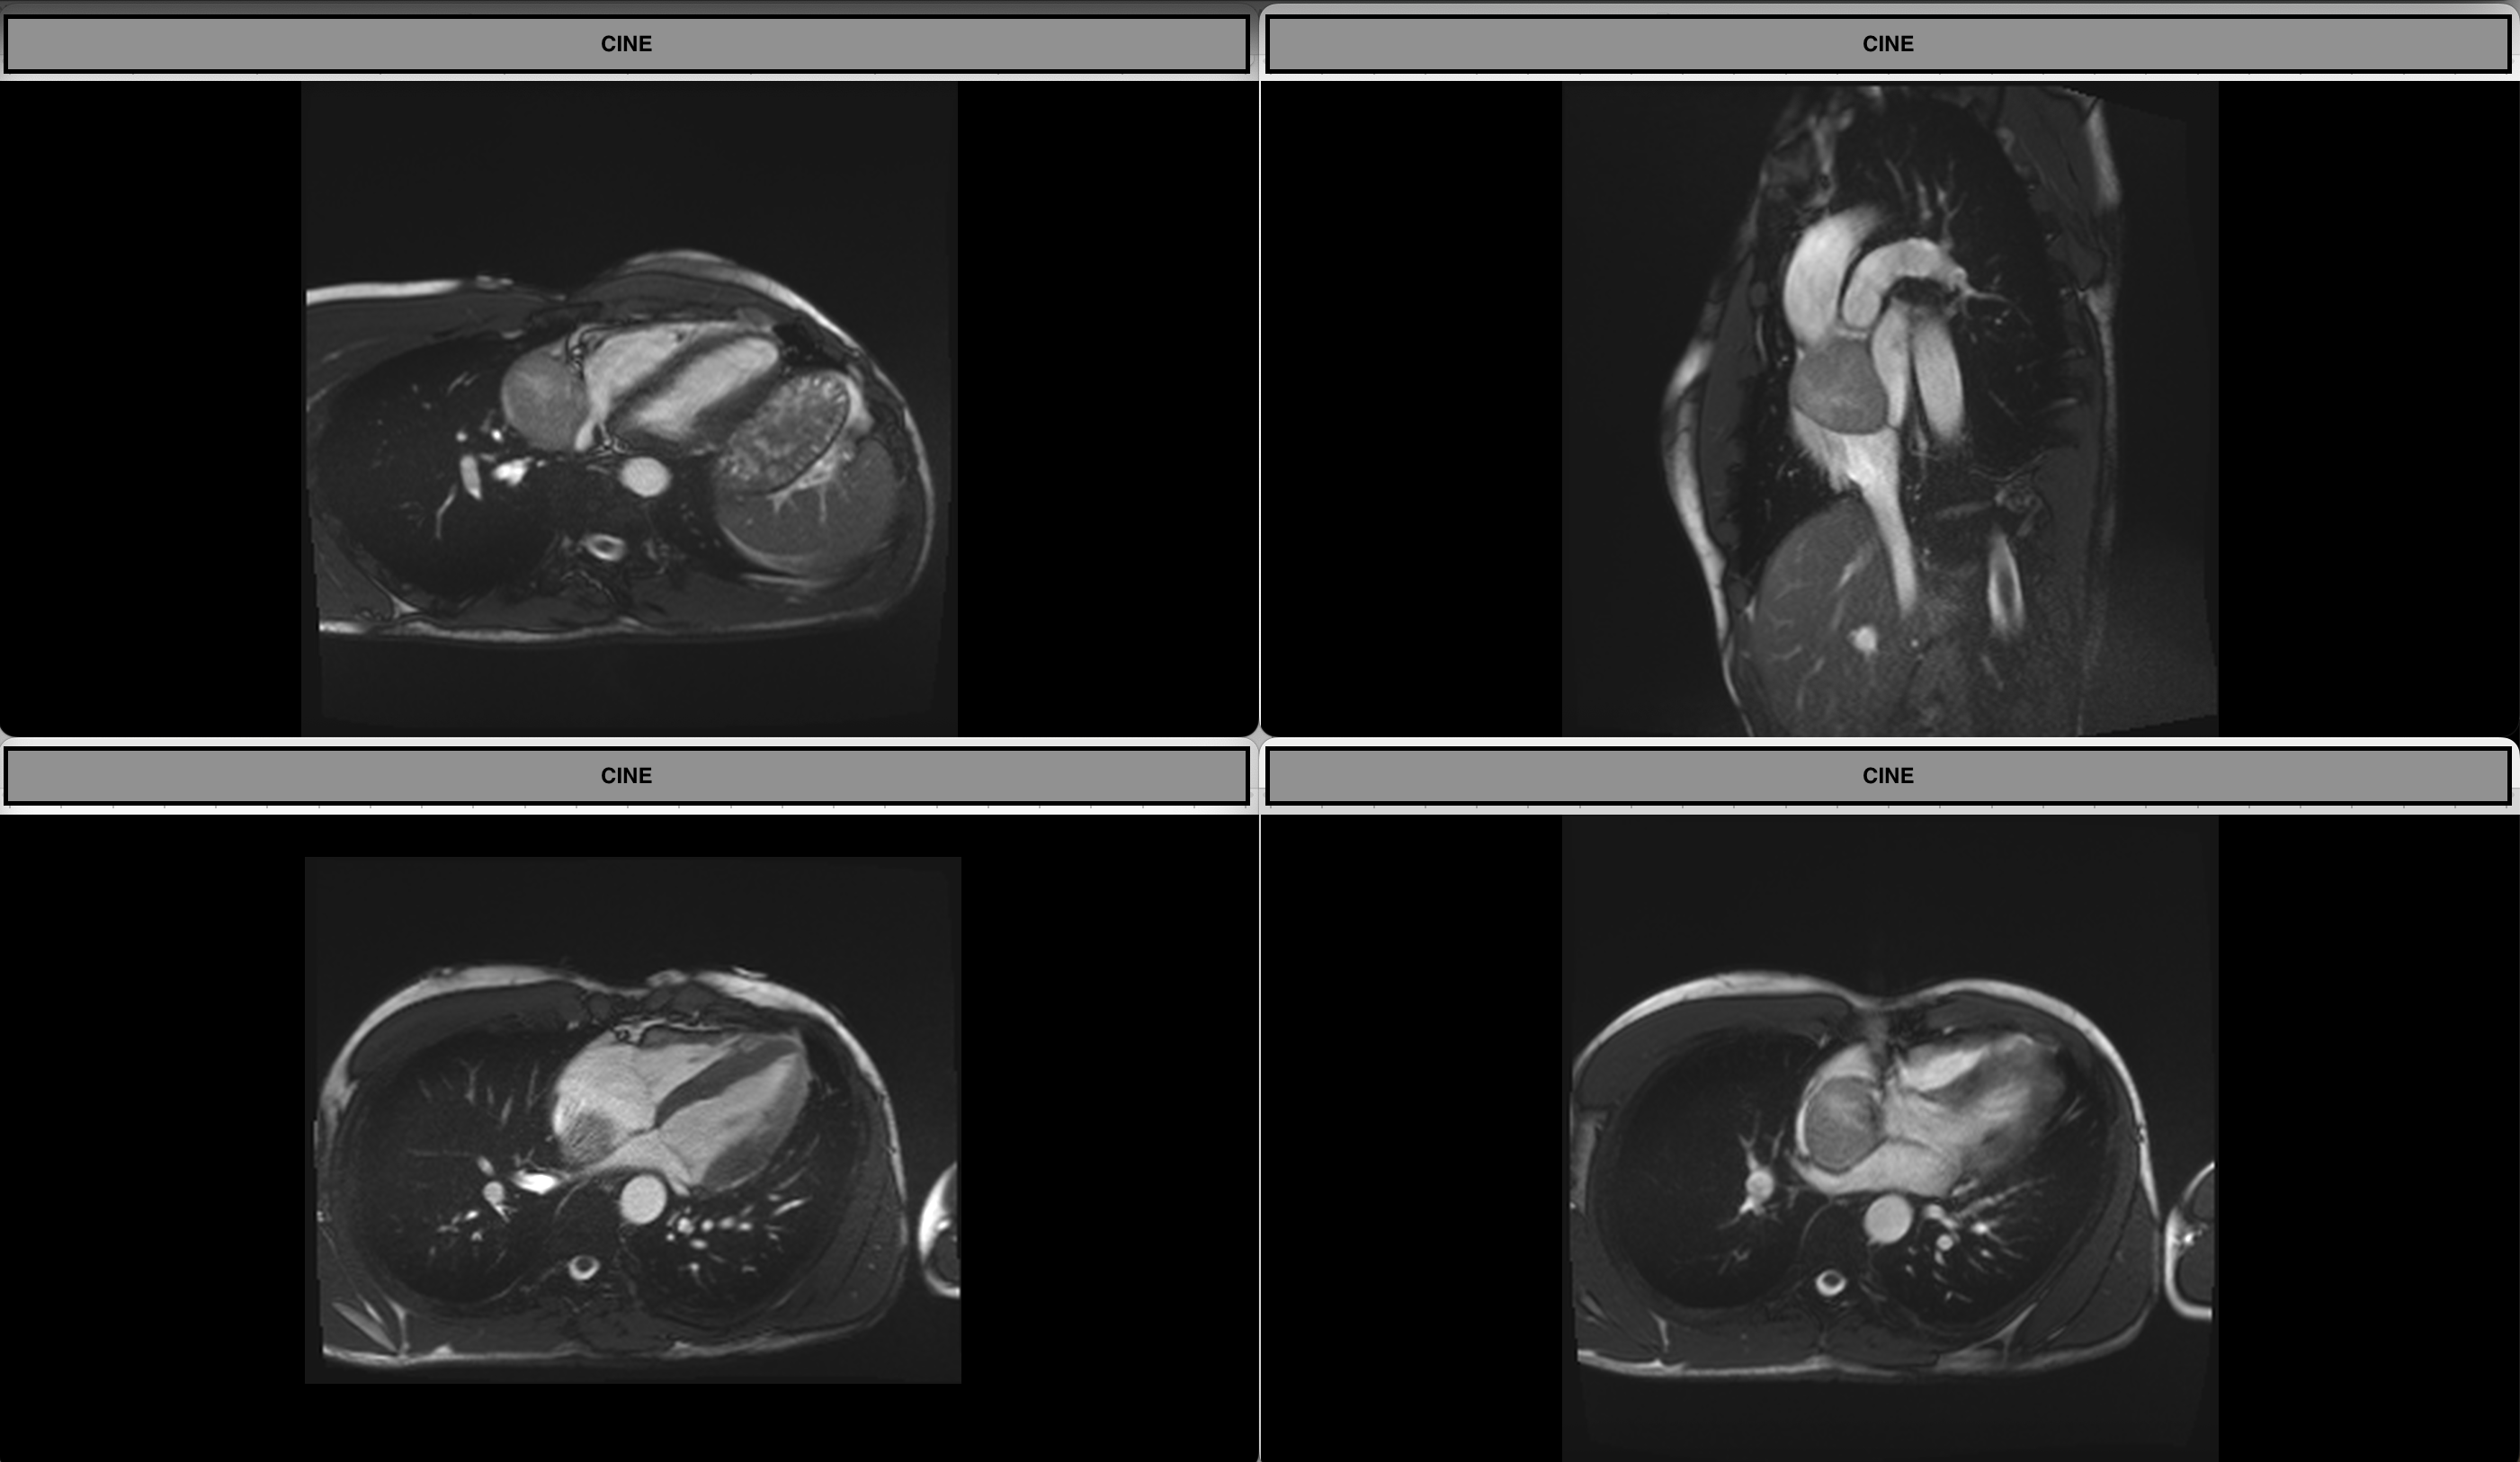

Cines

First-pass Perfusion